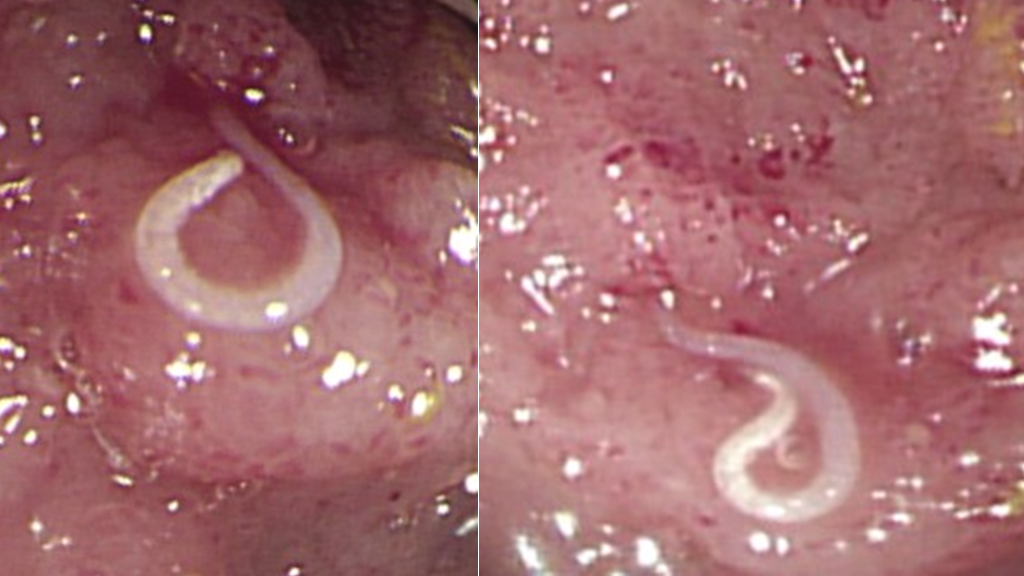

▲患者大腸裡的鉤蟲。(翻攝自許秉毅臉書)

台南市立安南醫院醫療副院長許秉毅近日表示,這名職業軍人在初步檢查時,白血球高到每毫升2萬4200顆,「嗜酸性紅白血球」比率甚至高達49%,這種狀況相當罕見,只有在嚴重過敏或寄生蟲感染時才會出現,而患者沒有過敏情形,糞便檢查也沒有發現寄生蟲卵,於是進一步作大腸鏡檢查。不料在大腸鏡下一看,不但大腸有多處紅腫,更驚人的是,大腸裡有多隻久違的「鉤蟲」在鑽動,令人怵目驚心。